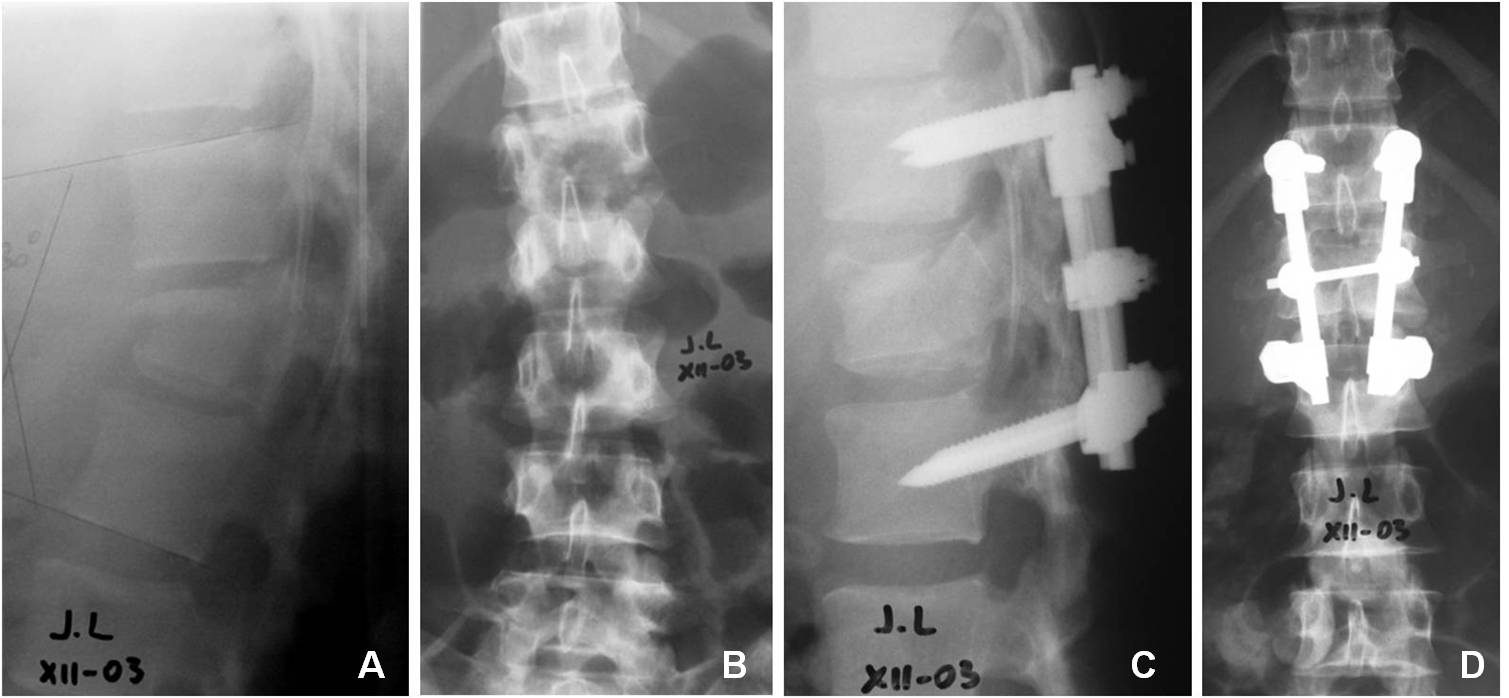

33. Petracchi M, Gruenberg M, Solá C, Ortolán E. Fracturas por estallido en columna dorsolumbar instrumentadas con tornillos

pediculares. Rev Asoc Arg Ortop Traumatol 2003; 68(4): 273-83.

34. Baños Clemente A, Ramirez Villaescusa J, Martinez Castroverde J, Martinez Arnaiz E, Andreés Gonzalez JM. Tratamiento

quirúrgico de fracturas toracolumbares por vía posterior con instrumentación y fusión bisegmentaria. Rev Esp Traumatol 2002;

37(210):84-88.

35. Parker JW. Successful short-segment instrumentation and fusion of thoracolumbar spine fracture. Spine 2000;25(9):1157-69.